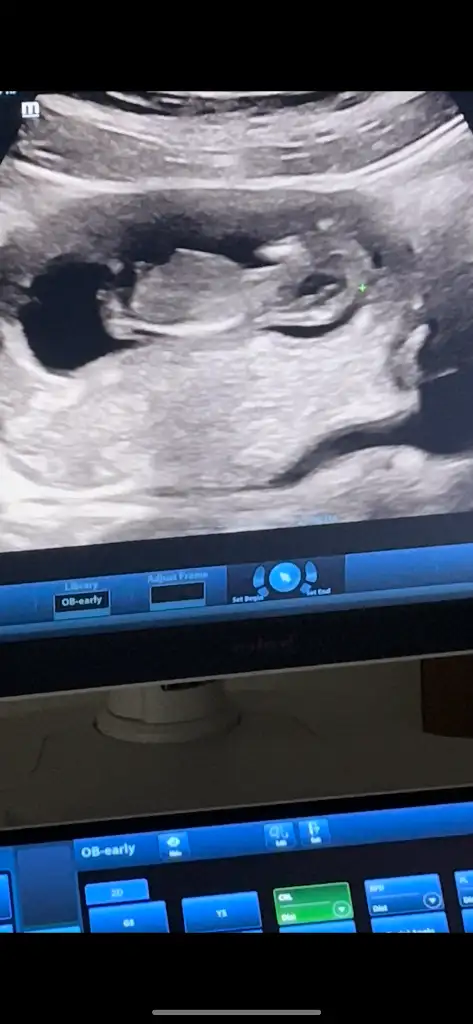

Bende çıkıntı gibi gördüm 19 haftada artık net bişey söylemesi gerekirdi19 haftalık doktor kıza benzetti ama bir cikinti var penise benzetmedim dedi

Benim 12 ve 13 haftalık görüntüye benziyor ama bana da kordon iki bacağının arasında yine de yüzde doksan erkek gibi dedi şu an 16 haftalık haftaya tekrar gidicem15+3 günlük doktor kıza benziyor dedi ama ben erkek görüyorom. Sizce?

Foto net diğil. Amma erkek gibi hiss etdim. Sizde 16-haftamı burda?Benim 12 ve 13 haftalık görüntüye benziyor ama bana da kordon iki bacağının arasında yine de yüzde doksan erkek gibi dedi şu an 16 haftalık haftaya tekrar gidicem